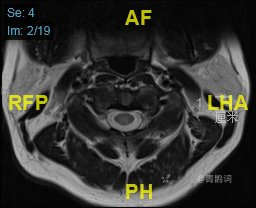

颈部磁共振平扫:

颈部磁共振平扫后增强: